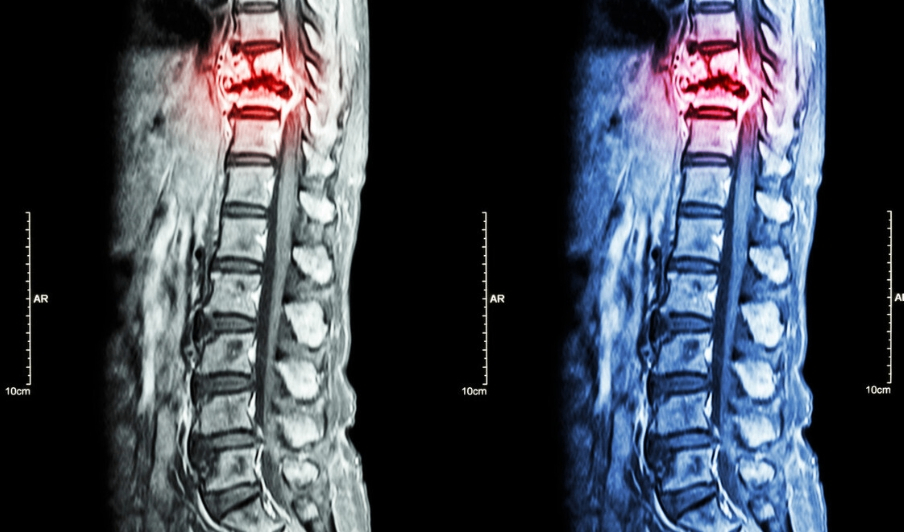

CT和MRI能够发现更早期的转移病灶,MRI尤其在判断脊柱转移癌是否压迫神经上更具优势。

经过核磁检查示:L1椎体及左侧附件异常信号。后又在北京大学人民医院查肿瘤标志物后,显示多项指标异常。